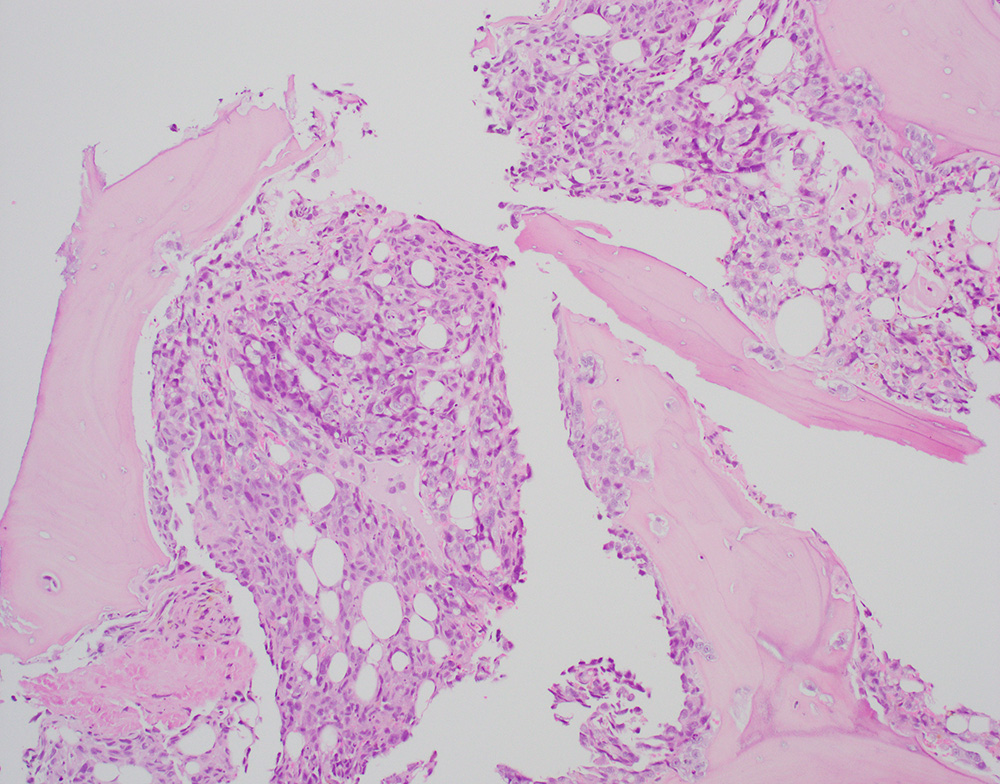

A bone biopsy showed a poorly differentiated epithelioid neoplasm with pleomorphic nuclei, prominent nucleoli (Figures-1, 2) with foci of necrosis. The tumor cells were positive for keratin 7 (Figure-3) with patchy positivity for pan-keratin, while they were negative for PAX8, SOX10, keratin 20, TTF-1, p40, NKX3.1, CDX2, and GATA3. Given the keratin positivity, the tumor was felt to represent metastatic carcinoma. The patient also had several skin nodules involving the posterior leg. A skin biopsy demonstrated numerous irregularly shaped anastomosing and infiltrative vascular channels lined by atypical endothelial cells (Figure-4). The neoplastic cells were positive for ERG, CD31 and CD34 (Figure 5). Re-evaluating and staining the bone biopsy with vascular markers showed positive ERG staining in the neoplastic cells.